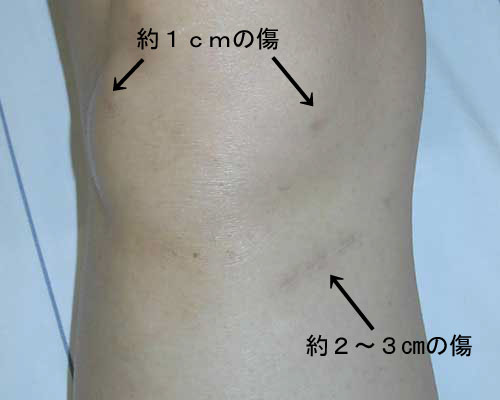

Acl 術後-靭帯再建術後 靭帯再建術後 ハムストリングスを用いて 作成した再建靭帯 手術直前 皮膚切開部のマーク 前十字靭帯が付着していた脛骨と 大腿骨の部分に直径5~9mmの 孔をあけて、その孔へ再建靭帯を 誘導した後、適切な緊張具合で靭 帯を固定します。以上より、acl再建術後では下肢アライメントとの関 係、pcl再建術後では膝屈曲運動との関係を主なキー ワードとして、再建靭帯に加わる牽引負荷を可及的に回 避してリハビリテーションが展開されているように思わ れる。

ようやくタイトル内容に行きつきましたが 「ACL(前十字靭帯再建手術)後の抜釘手術は行うべきか? 」 という事です。 上記でも少し触れましたが僕は3年前に 右膝前十字靭帯の断裂を経験 しまして、再建する手術を行っているのです。 抜釘とは手術時退院から復帰まで ※運動能力、術創部の回復レベルに個人差があるため、医師の判断で開始時期が多少前後することがあります。 ※術後 5 ヶ月から 1 ヶ月おきに筋力測定、靱帯の機能検査(KNEELAX)を行います。 ※正座は術後 6 カ月でできるように調整し術後3ヶ月からのリハビリ オバーヘッド・スクワット スプリット・スクワット ニーベント・カーフレイズ(壁) ニーベント・カーフレイズ(棒) 片脚ニーベントカーフレイズ 片脚スクワット(キープ) 片脚コンビネーション